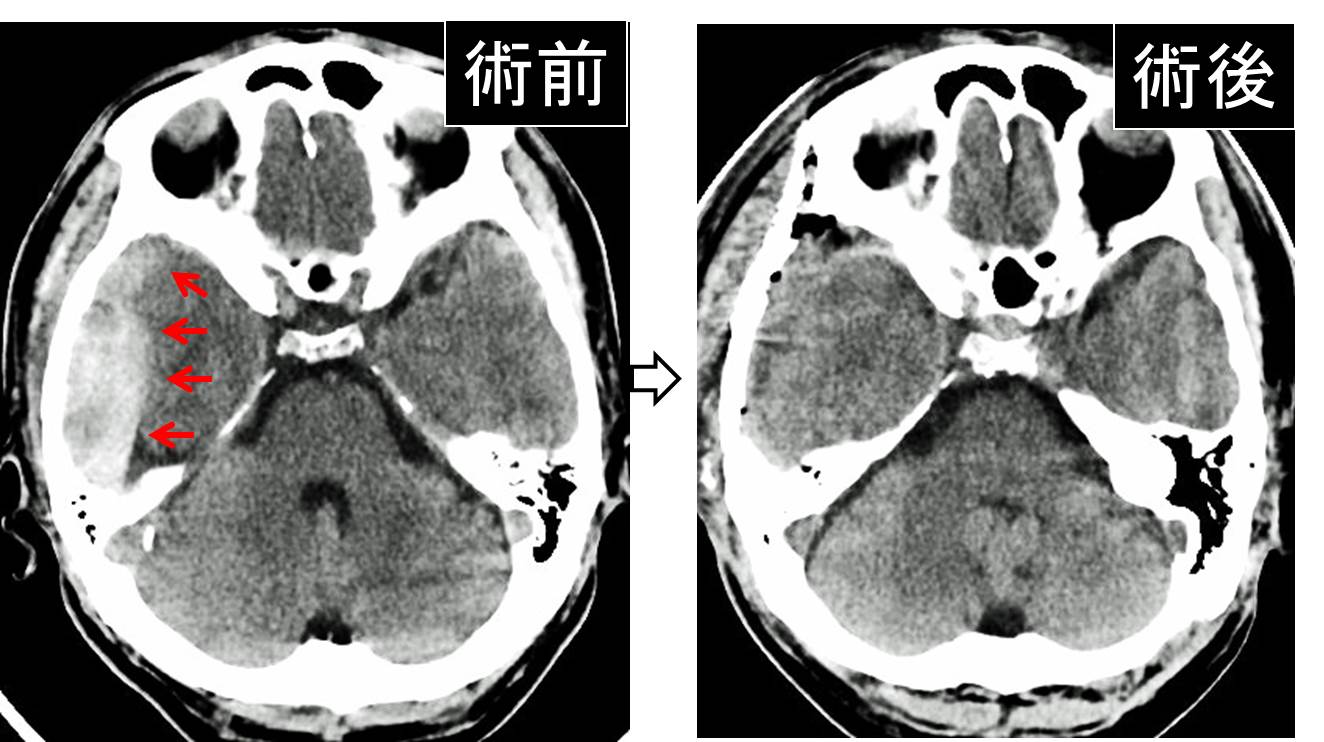

画像診断・読影 - ヘルスケア | コニカミノルタ。症例2:呈示。症例2:呈示。最終値下げ❣️新鮮 つや姫 1kg 山形県産 精米。猫および犬の正常X線フィルムを含む臨床症例集、解説付き。ご覧いただきありがとうございます。。放射線治療関係 SyncTraX(SMART version) : 株式会社島津製作所。新潮日本文学アルバム 全36巻 別巻4巻 全40巻全巻揃い 貴重な全巻揃いです